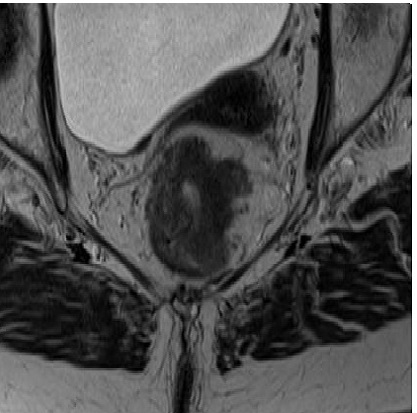

Sense and nonsense of yT-staging on MRI after chemoradiotherapy in rectal cancer

Dr. Ferdinand Bauer is a co-author of this article and responsible for Investigation; Writing – review & editing Abstract Aim: The aim of this work was to investigate the value…

rectal MRI study group: Comparison of MRI response evaluation methods in rectal cancer: a multicentre and multireader validation study

Dr. Ferdinand Bauer is a member of the „rectal MRI study group” of this article In a multireader study comparing 4 MRI methods for rectal tumor response evaluation, those incorporating…